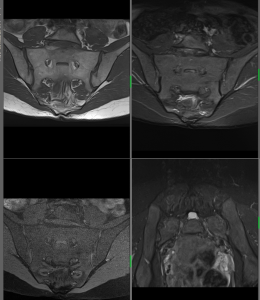

MR v břišní a pánevní oblasti

Diferenciální diagnostika jaterních lézí, cholangiopankreatografie – tzv. MRCP (neinvazivní obdoba ERCP), diferenciální diagnostika tumorů pankreatu, ledvin, staging karcinomu děložního čípku a endometria, staging karcinomu rektosigmatu, MR enterografie (u Crohnovy choroby).Rovněž se ve spolupráci s Urologickým oddělení Nemocnice České Budějovice a se specialisty místními a z okolních regionů specializujeme na diagnostiku karcinomu prostaty.

Na našem pracovišti provádíme vyšetření mozku, orbit, hypofýzy, krční páteře, hrudní páteře, bederní páteře, kolenního kloubu, ramenního kloubu, jater a pankreatu, MRCP, ledvin a nadledvin, pánve, MR enterografii, MR angiografii intrakraniálních tepen, MR angiografii mozku – venózní, MR angiografii karotid, MR angiografii tepen dolních končetin, MR angiografii renálních tepen a vyšetření ostatních kloubů těla.